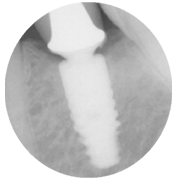

The unique friction-lock and keyed TissueCare connection creates such a close fit between the two components that subcrestal implant placement is possible. This leads to a positive bone response, enabling the desired emergence profile and transgingival healing.

In other words, Ankylos offers the versatility of a twopiece system while maintaining healthy hard and soft tissue and keeping it free from irritation.